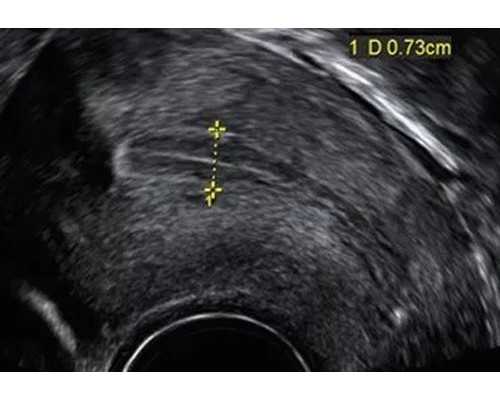

1、怀孕满6周,B超确认孕妇的胚牙( CRL)需达到5MM,且见到心管博动,才可进行测试。